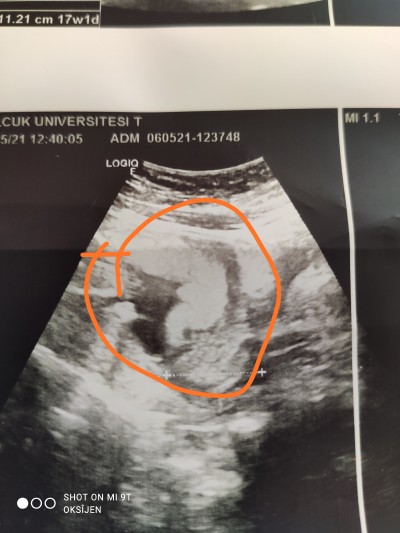

Kızlar 15 haftalık hamileyim bu gün ki ultrason görüntüsü işaretledigim yer bebek resmi mi bana mı öyle geliyor :)

Gebelik haftası 15+0

Canim orda isaretli yer var ya ölçum yapmis doktor bebek orda

O bebek canım hatta plasenta da karşısında dikkat edersen bebeğe doğru ip gibi kordon uzuyor:)